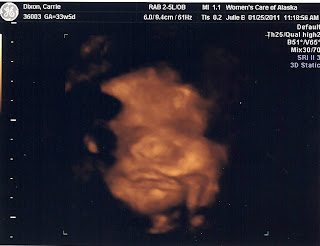

Since my belly measured 37 weeks at my 33 week appointment, we had an ultrasound to determine if it is a big baby or lots of fluid. It's a big baby! Per his measurements, he weights 5 lbs. and 14 oz. He is the size of an average 35 week and 4 day fetus. He's only 33 weeks and 6 days! The ultrasound machine moved my due date up to February 25th. I will talk with Dr. Counts on the 1st to decide if we will induce early because of his size. His heart rate was 149 bpm which is perfect. He is head down and still shy. He did not want to show his face...again. The ultrasound pics weren't as clear this time since he's running out of room!